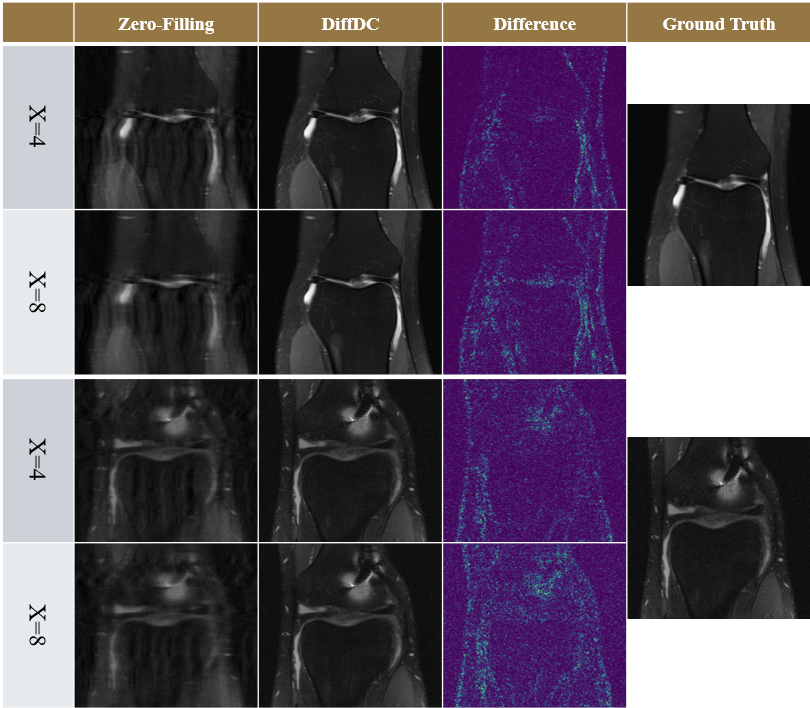

V-D Generalization Across Acceleration Factors

To demonstrate the adaptability and generalization capability of the proposed approach, we evaluate MRI reconstruction performance under different acceleration factors. Specifically, we examine reconstruction results at an acceleration factor of 4 using various sampling patterns, even though the DiffDC model was trained exclusively at an acceleration factor of 8. As shown in Fig. 5, DiffDC significantly improves reconstruction quality under these conditions, highlighting its robustness to changes in undersampling rates.

This adaptability underscores the model’s ability to generalize beyond its training configuration, reconstructing high-quality images with preserved details and reduced artifacts across diverse scenarios. Such versatility makes DiffDC particularly suitable for clinical applications where sampling conditions may vary dynamically. Fig. 6 further compares the performance of the proposed approach, DiffDC, at acceleration factors of 4 and 8, showcasing the square root difference between the reconstructed images and the undersampled images. These comparisons provide additional evidence of the effectiveness and generalization capabilities of the proposed model, demonstrating its ability to deliver high-quality reconstructions across varying acceleration factors. Table II presents the performance metrics of the proposed DiffDC model, including PSNR, SSIM, and LPIPS. These results further highlight the effectiveness of the DiffDC model.

Refer to caption

Figure 6: MRI reconstructions with an acceleration factor of x = 4 using the proposed model (DiffDC) trained at an acceleration factor of x=8, and sampling patterns (Sampling-Ptn): Gaussian 1D (G1D), Gaussian 2D (G2D), Uniform 1D, and Poisson.